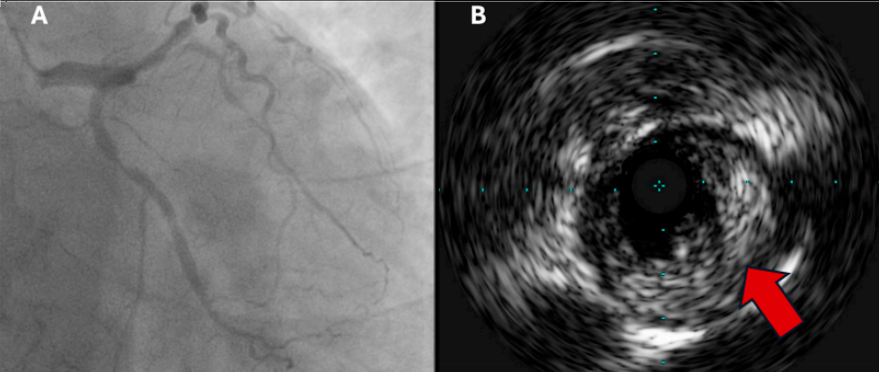

图1 (A)与急性冠状动脉综合征后发生短暂性新发房颤的患者相比,无房颤患者的MACE(缺血性卒中、复发性房颤或全因死亡率)风险;(B)MACE的漏斗图。AF,房颤;MACE,主要不良心血管事件。